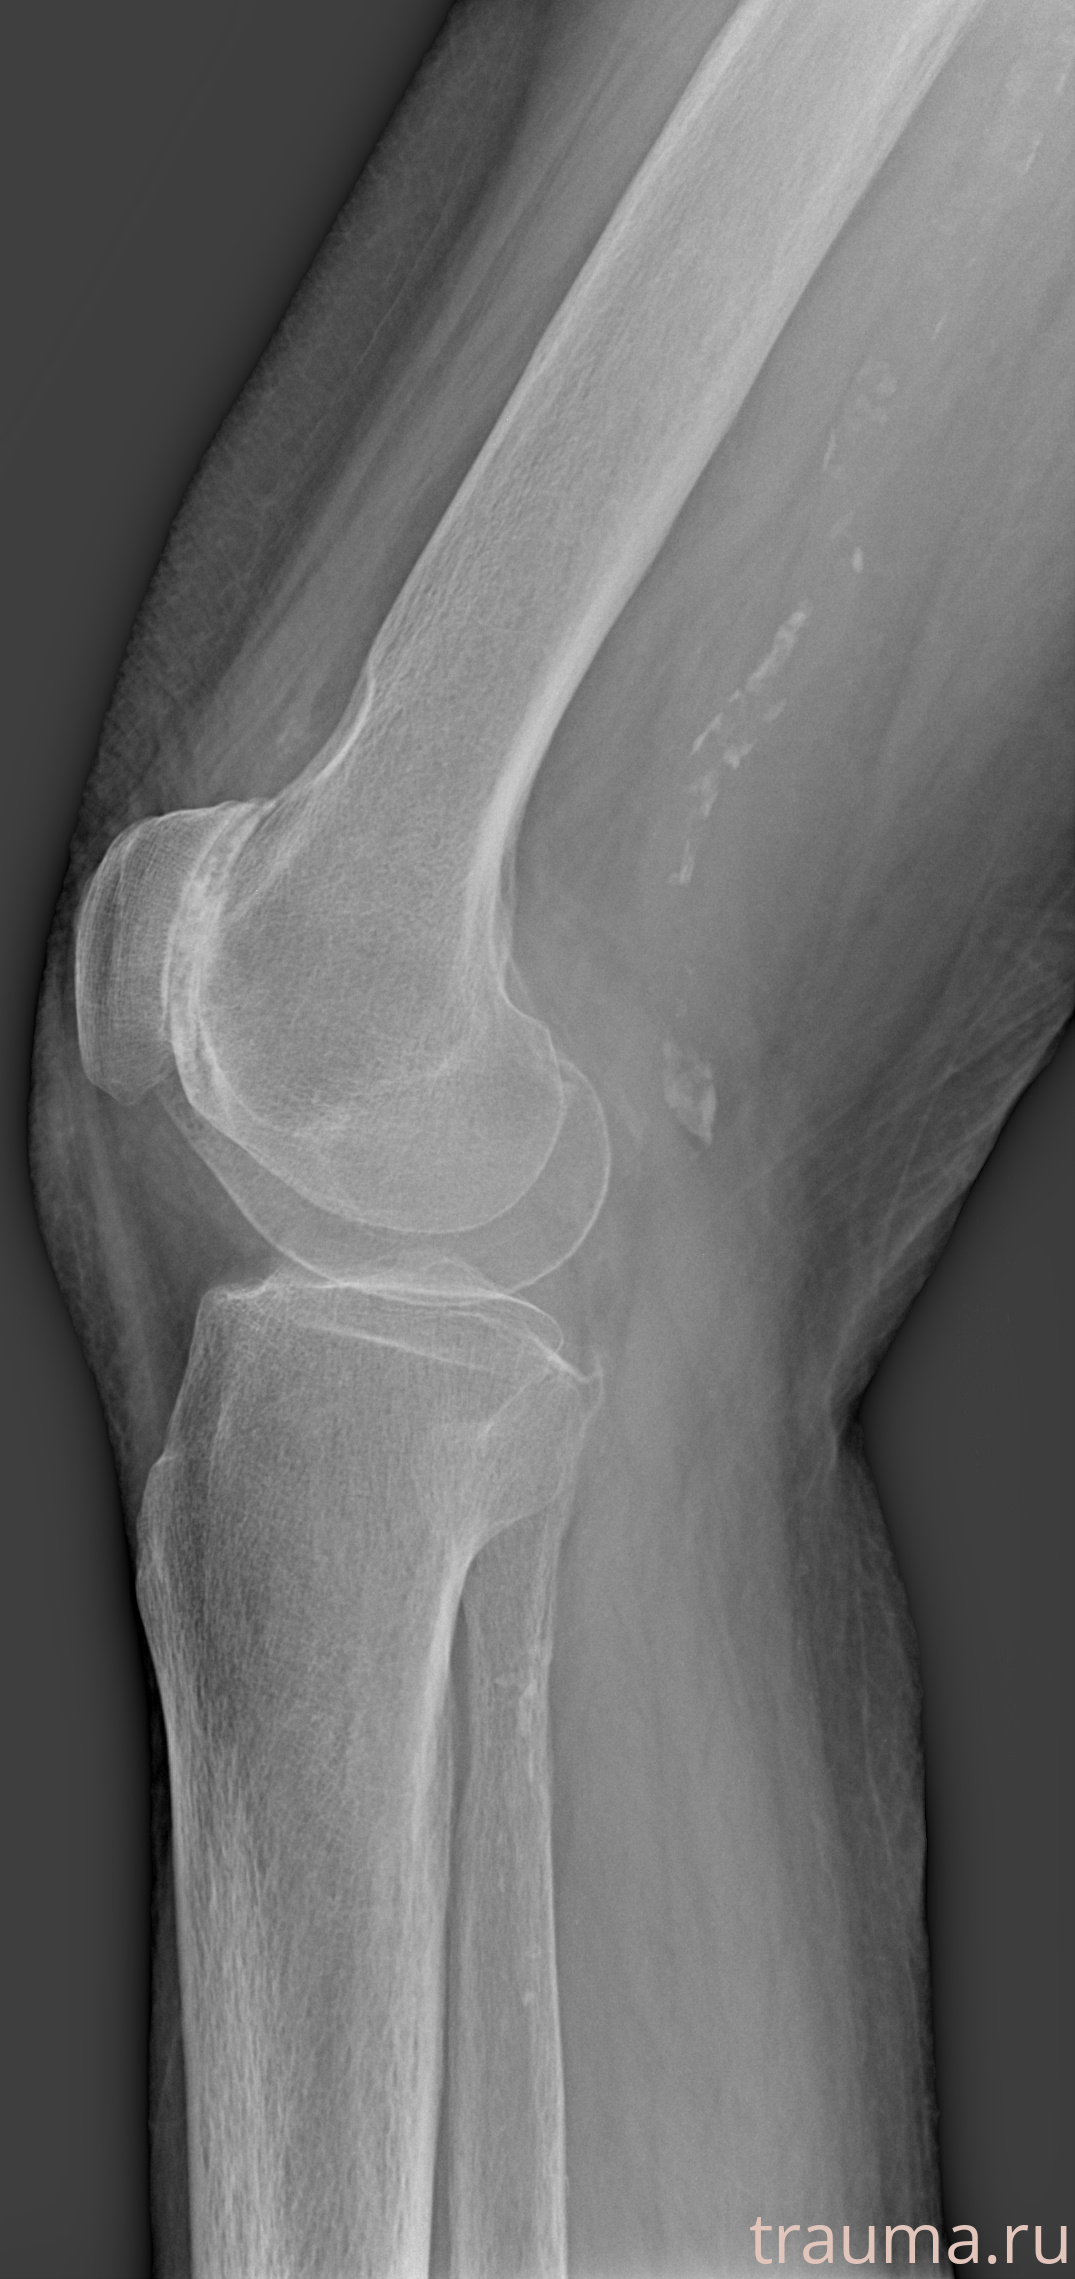

Рентгенограммы

Рентген на дому: по вашему адресу приезжает врач-рентгенолог, травматолог-ортопед с мобильным рентгеновским аппаратом, проводит диагностику травмы или заболевания, делает необходимые рентгенограммы, дает рекомендации по дальнейшему лечению. Получить качественные снимки в домашних условиях возможно благодаря уникальной методике, разработанной МосРентген Центром для института  Склифосовского